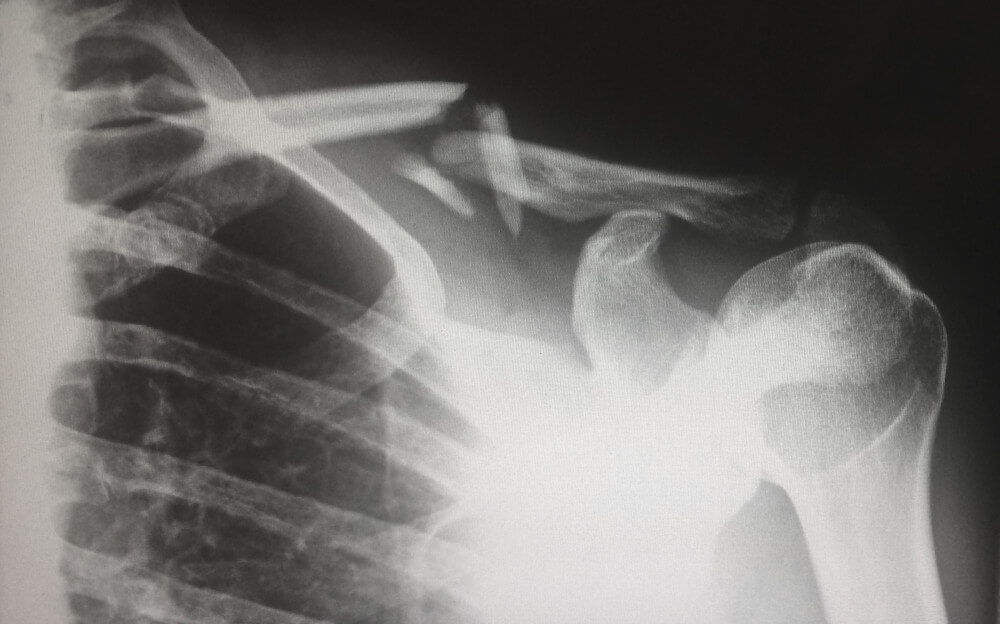

Your limb bends in a way it shouldn't as it breaks!